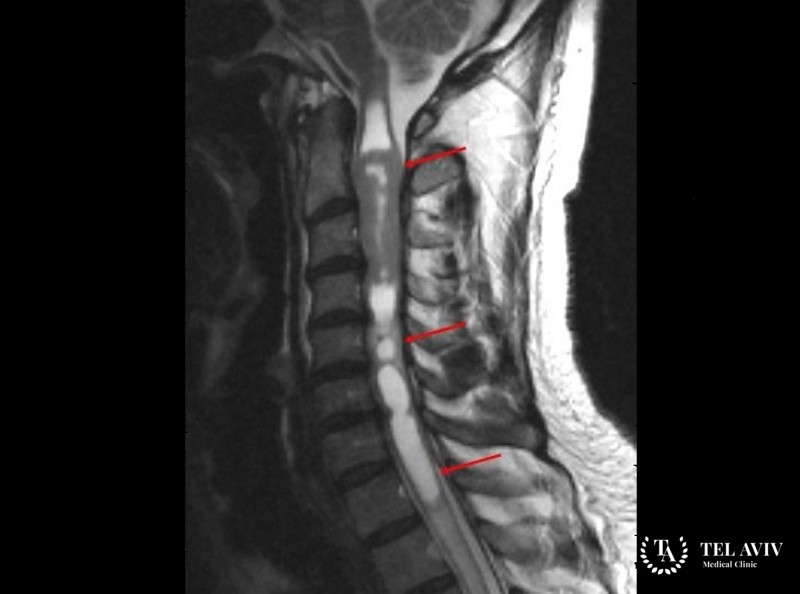

Как проводится диагностика и лечение шванномы?

Для диагностирования неврологического заболевания в Tel Aviv Medical Clinic применяются комплексные способы обследования. Наиболее информативную оценку можно получить, используя современную аппаратуру:

- МРТ, КТ.

Диагностика позволяет определить степень распространенности новообразования, его структуру, размер, глубину и форму, и уже на основании результатов разрабатывать оптимальную тактику лечения. Также, врачами нашей клиники при выборе терапевтических мер учитывается состояние пациента, сопутствующие болезни и осложнения. Лечение шванномы предполагает ее удаление. Это может быть сделано открытым хирургическим вмешательством, эндоскопическим и малоинвазивным путем. При расположении опухоли в труднодоступном месте специалисты Tel Aviv Medical Clinic используют безопасную технику радиохирургии, направленную на уничтожение больных клеток.